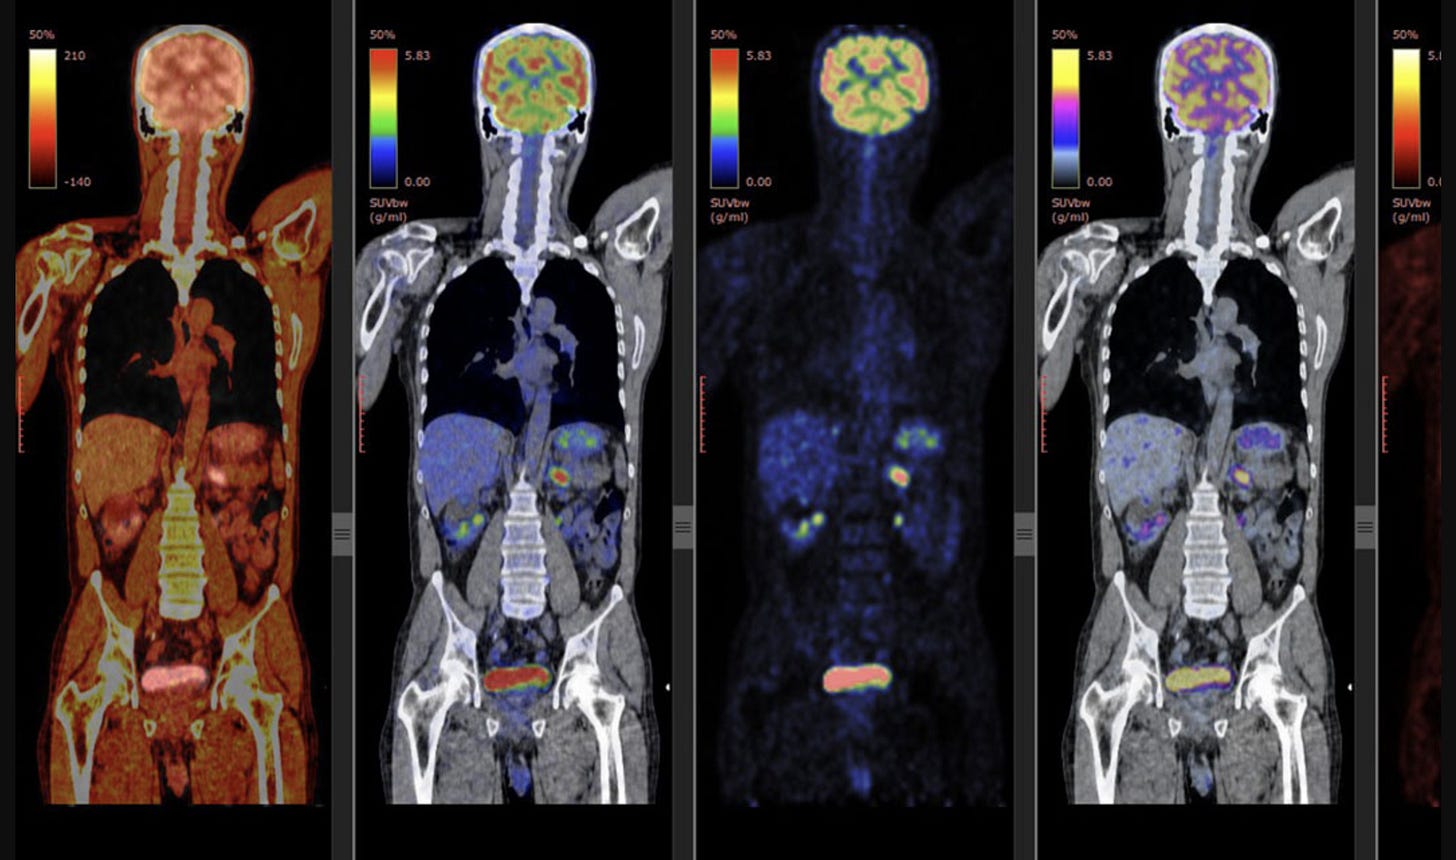

PET scans provide a different layer of information. Rather than focusing on structure, they assess metabolic activity. We often describe this activity as “hot” or “cold.”

Most PET scans in oncology use a glucose-based radiotracer called FDG. Because many cancer cells have altered metabolism and increased glucose uptake, areas of active disease often appear “hot” as regions of increased signal activity. This can allow PET scans to identify disease that may not yet be causing obvious anatomic changes on CT. This can be quantified as well, and this is where you see “SUV” or standard uptake value often on the PET scan reports.

This sensitivity is also what makes PET scans more challenging to interpret. FDG uptake is not specific to cancer. Inflammation, infection, tissue repair, and certain autoimmune or inflammatory conditions can all produce increased signal. Sarcoidosis is a classic example of a benign condition that can closely mimic malignancy on PET imaging.

Spatial resolution can affect things as well. For a lesion to be reliably detected on PET, it generally needs to be on the order of a centimeter or larger. Small lesions can appear PET-negative even when they are cancerous. A normal PET scan does not mean cancer is absent at a microscopic level. It means there is no metabolically active disease large enough to be detected.

PET scans expose patients to more radiation than CT alone and are more expensive. For that reason, they are typically reserved for situations where metabolic information is likely to change management. This is particularly true in cancers like lymphoma and sometimes melanoma, where treatment response can be better reflected by changes in activity than by changes in size, and where skin or soft tissue disease can be difficult to assess with CT alone.